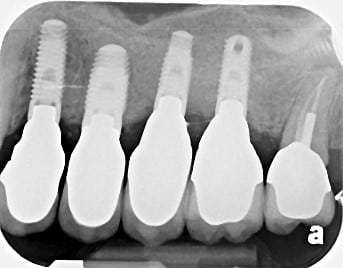

An external sinus lift, where there is very little or no bone to work with, is performed before the actual implant placement and usually covers the floor of the sinus on one side below its protective membrane.

An example of an external sinus lift can be seen below:

Stage 1: No Bone Available to Receive any Implant

Stage 2: Bone Graft Placed in an External Sinus Lift

Stage 3: Implants Placed in the Matured Bone Graft